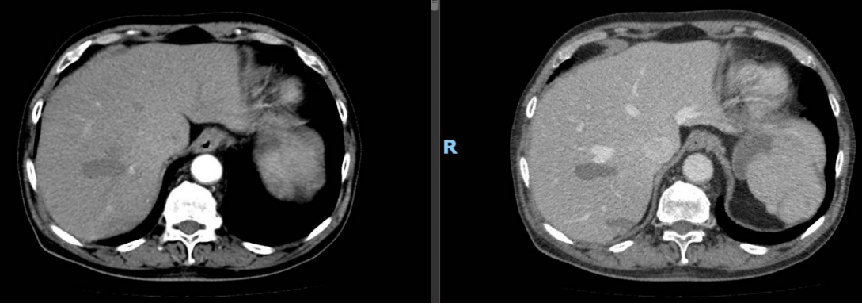

影像学检查:

CT:肝S5肝细胞癌,大小约55×68×55mm,有假包膜,另胆囊结石

动脉期:

静脉期:

冠状面: